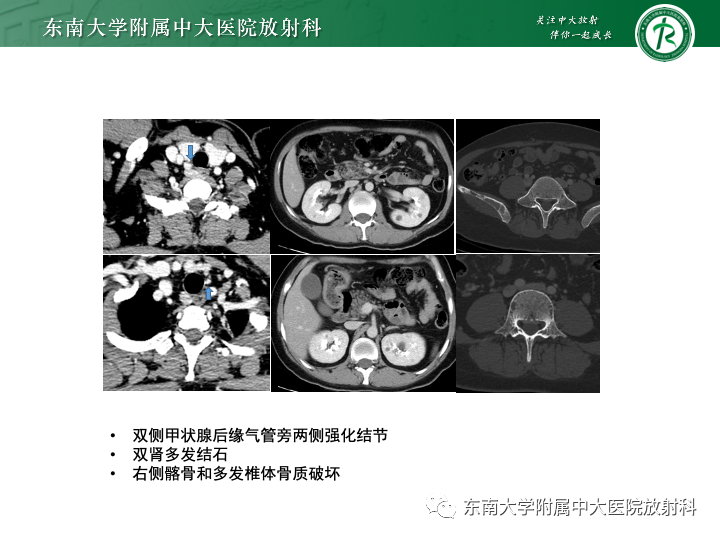

•女,75岁

•主诉:骨痛伴尿泡沫增多1月,加重10余天

•实验室检查:尿常规:蛋白2+,隐血2+;血生化检查:Ca:2.97mmol/L;总蛋白:88.8g/L;LDH:356U/L;肌酐:84umol/L